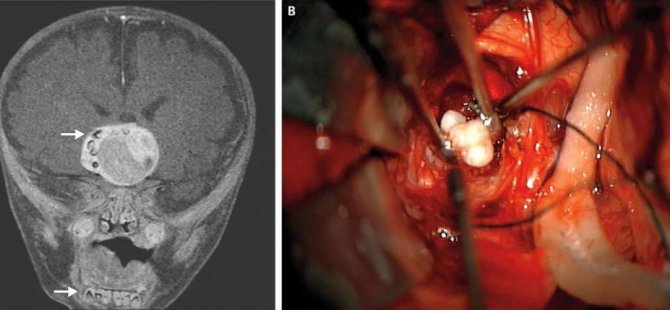

2014 yılında yaşanan vakada, Maryland Üniversitesi ve Johns Hopkins Çocuk Merkezi’nden nörocerrahlar, 4 aylık bir bebeği MRI beyin taramasından geçirdi.

Tarama işlemleri sonucunda çocuğun beyninde ceviz büyüklüğünde bir tümör keşfetti. Tümörün sağ tarafında ise çok sayıda küçük çıkıntı göze çarpıyordu. Bebeği hızla ameliyata alan cerrahlar tümörü aldı. Büyüyen kısmın craniopharyngioma adı verilen, embriyotik dokunun dönüşümüyle ortaya çıkan bir beyin tümörü olduğu ortaya çıktı. Genelde beynin hormon salgılama merkezine yakın olan bu yapılar, vakaların çok büyük bir kısmında salih tümörler oluyor (yani kansere dönmeyen ve yayılmayan çeşit) ancak hormonal merkeze yaptıkları baskı nedeniyle sorun yaratabiliyorlar.

Ancak vaka ile ilgili ilginçlikler bununla sınırlı kalmadı. Cerrahlar, tümörde birkaç tane tamamen gelişmiş diş buldular. Teratoma olarak bilinen bu yapılar, genelde farklı doku türleri bulundurabiliyorlar. Bu dokular saç, kas, kemik gibi farklı türlerden olabiliyor. Yine de doktorlar neden bu tümör üzerinde diş oluştuğunu bilmiyor.

Ancak vaka ile ilgili ilginçlikler bununla sınırlı kalmadı. Cerrahlar, tümörde birkaç tane tamamen gelişmiş diş buldular. Teratoma olarak bilinen bu yapılar, genelde farklı doku türleri bulundurabiliyorlar. Bu dokular saç, kas, kemik gibi farklı türlerden olabiliyor. Yine de doktorlar neden bu tümör üzerinde diş oluştuğunu bilmiyor.